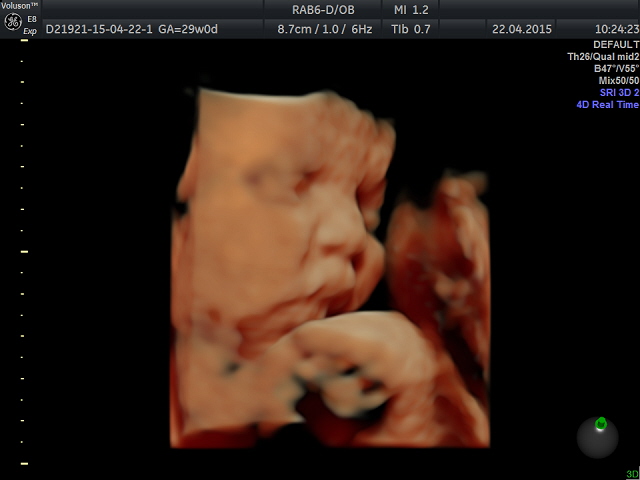

Была на очередном приему сегодня. Вес 60,5 прибавка за 3 недели 1,9 кг. за всю беременность 10,3 кг. ВДМ 30, +3 см с прошлого приема. Сделали мы УЗИ и 4Д УЗИ. Девочка наша красавица, уже щекастая, деловая лежит, глаза открывала, пальцы сосала, улыбалась))) в общем какая прелесть))) Мужу говорю, по-моему у нее твой нос, последовал ответ "это засада", поясню у мужа нос картофилина)))) мы все не могли нарадоваться, что у сыночка мой носик))) Ну а в целом на меня похожа))) такая же

деловая)))

Совсем забыла параметры записать. Окружность головы 79мм, живота 80мм, длинна бедра 54мм. Судя по всему девочка крупная)) так как срок 28,4 а по УЗИ ставят 29-30 недель.